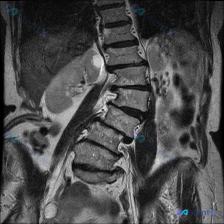

整理了一份腰椎MRI的读片讨论资料,先看冠状位T2加权像的客观表现: 1. 脊柱排列:腰椎向左侧凸(Levoscoliosis),椎体有旋转,中轴线不平直 2. 椎间盘:多节段下腰椎T2信号明显减低(“黑盘”征),提示脱水退变;凹侧(左侧)椎间隙更窄,有挤压 3. 椎体/软组织:椎体边缘有骨赘;骨髓...

整理了一份影像病例资料,大家先看看: 核心影像表现(腰椎MRI T2冠状位): 1. 腰椎序列左侧弯畸形,椎体排列基本连续 2. L2/3、L3/4、L4/5椎间隙不对称性变窄(左侧更甚) 3. 多节段椎间盘T2弥漫性低信号,提示脱水、变性 4. 侧弯凹侧小关节信号及结构紊乱 5. 双侧髂嵴高度不对...

整理了一份腰椎MRI(T2序列冠状位)的影像资料,先给大家说几个关键发现: 1. 脊柱整体形态:腰椎序列向左侧凸,椎体序列基本连续,未见明显单节段严重滑脱; 2. 椎间盘改变:腰椎下段多个椎间盘T2信号减低,椎间隙高度不均匀狭窄,左侧(凹侧)更明显; 3. 椎间孔情况:左侧(凹侧)椎间孔有不同程度狭...

整理到一份腰椎影像分析资料,第一眼很容易被「脊柱侧弯」吸引,但再仔细看会发现一个容易被忽略的「跨学科线索」。 先放核心影像表现(冠状位T2WI): 1. 脊柱序列:腰椎向左侧突,椎间隙左右不等宽 2. 椎间盘:下腰椎(L3-L4、L4-L5为主)T2信号明显减低(黑盘征),部分节段侧向变窄,椎体边缘...